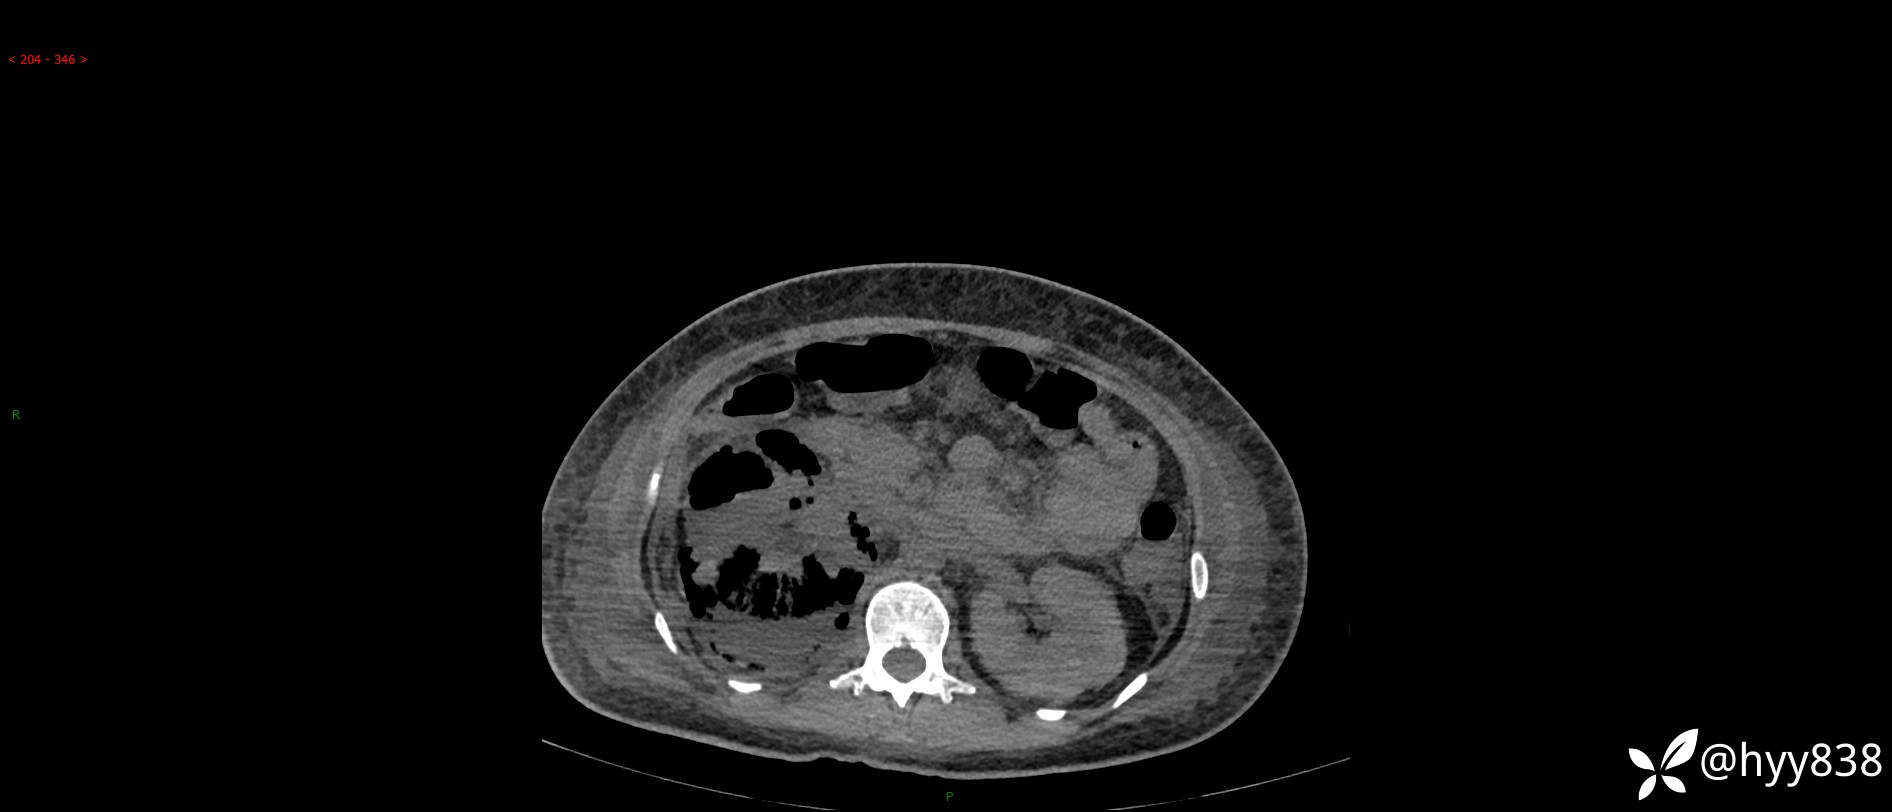

大年三十︱年轻女性,饮酒后突发腰痛,很意外---结果公布~

患者年龄:29岁

主诉:右侧腰部疼痛2天

简要病史:患者2天前和朋友聚餐饮酒时出现右侧腰部疼痛不适,呈间断性胀痛,伴发热、呕吐,无头晕、心慌、胸闷等不适,不伴有尿频、尿急、尿痛等症,院外与当地诊所输液对症治疗症状未见明显改善,今来我院急诊就诊全腹部CT自阅片考虑右肾周围炎,现患者为寻求进一步就诊,来我科就诊,我科以“右肾周围炎”收治入院。 起病以来,患者精神、饮食、睡眠可,大小便正常,体力体重无明显减轻。

临床诊断:肾周围炎

肾脏CT平扫